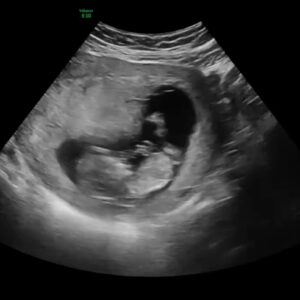

Porodna zgodba – tretjič

Mojo že tretjo porodno zgodbo začenjam s soboto 17. januarjem in občutkom, da je skrajni čas za pripravo torbe za v porodnišnico. S pakiranjem sem odlašala do zadnjega, saj mi je misel na…

Bil je četrtkov večer pred pregledom nuhalne svetline v tretji nosečnosti. Ker smo v postopku manjše renovacije, je bilo stanovanje v čistem razsulu. Po današnji neposrečeni montaži klime ni šlo nič več po…

Carski rez- easy way out?

Svojo porodno zgodbo vsakič povem malo drugače, ker jo s časoma tudi dojemam drugače in lahko povem, da več časa kot mine od takrat, manj njenih neprijetnih trenutkov se spomnim. Zadnjič pa mi…

Okrevanje po carskem rezu in sprejemanje nove sebe

Že kar nekaj časa je minilo odkar sem se nazadnje usedla za računalnik in odločila opisati delček moje poti do sedaj. Ta blog pa mi je še posebej pri srcu, saj je razlog,…